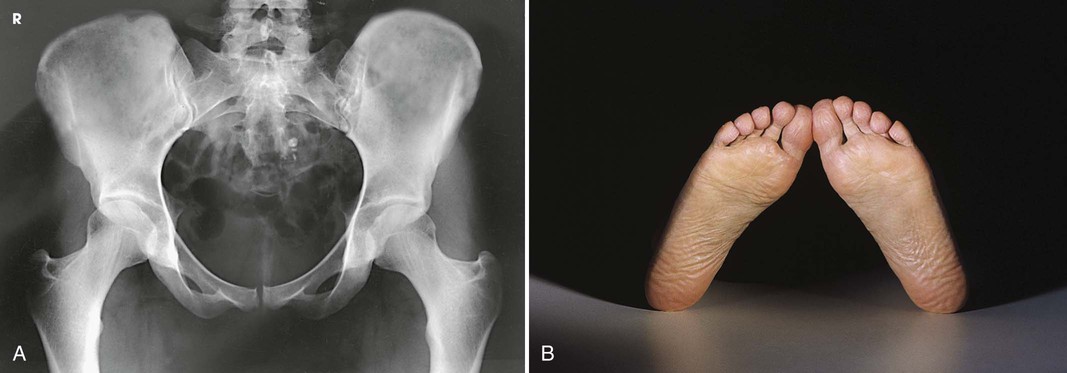

Structures shown

The image shows an AP projection of the pelvis and of the head, neck, trochanters, and proximal one third or one fourth of the shaft of the femora (Fig. 7-18).

Martz and Taylor1 recommended two AP projections of the pelvis to show the relationship of the femoral head to the acetabulum in patients with congenital dislocation of the hip. The first projection is obtained with the central ray directed perpendicular to the pubic symphysis to detect any lateral or superior displacement of the femoral head. The second projection is obtained with the central ray directed to the pubic symphysis at a cephalic angulation of 45 degrees (Fig. 7-19). This angulation casts the shadow of an anteriorly displaced femoral head above that of the acetabulum and the shadow of a posteriorly displaced head below that of the acetabulum.